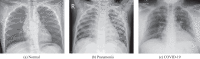

Objective: One of the critical factors behind the rapid spread of COVID-19 pandemic is a lengthy clinical testing time. The imaging tool, such as Chest X-ray (CXR), can speed up the identification process. Therefore, our objective is to develop an automated CAD system for the detection of COVID-19 samples from healthy and pneumonia cases using CXR images.

Methods: Due to the scarcity of the COVID-19 benchmark dataset, we have employed deep transfer learning techniques, where we examined 15 different pre-trained CNN models to find the most suitable one for this task.

Results: A total of 860 images (260 COVID-19 cases, 300 healthy and 300 pneumonia cases) have been employed to investigate the performance of the proposed algorithm, where 70% images of each class are accepted for training, 15% is used for validation, and rest is for testing. It is observed that the VGG19 obtains the highest classification accuracy of 89.3% with an average precision, recall, and F1 score of 0.90, 0.89, 0.90, respectively.